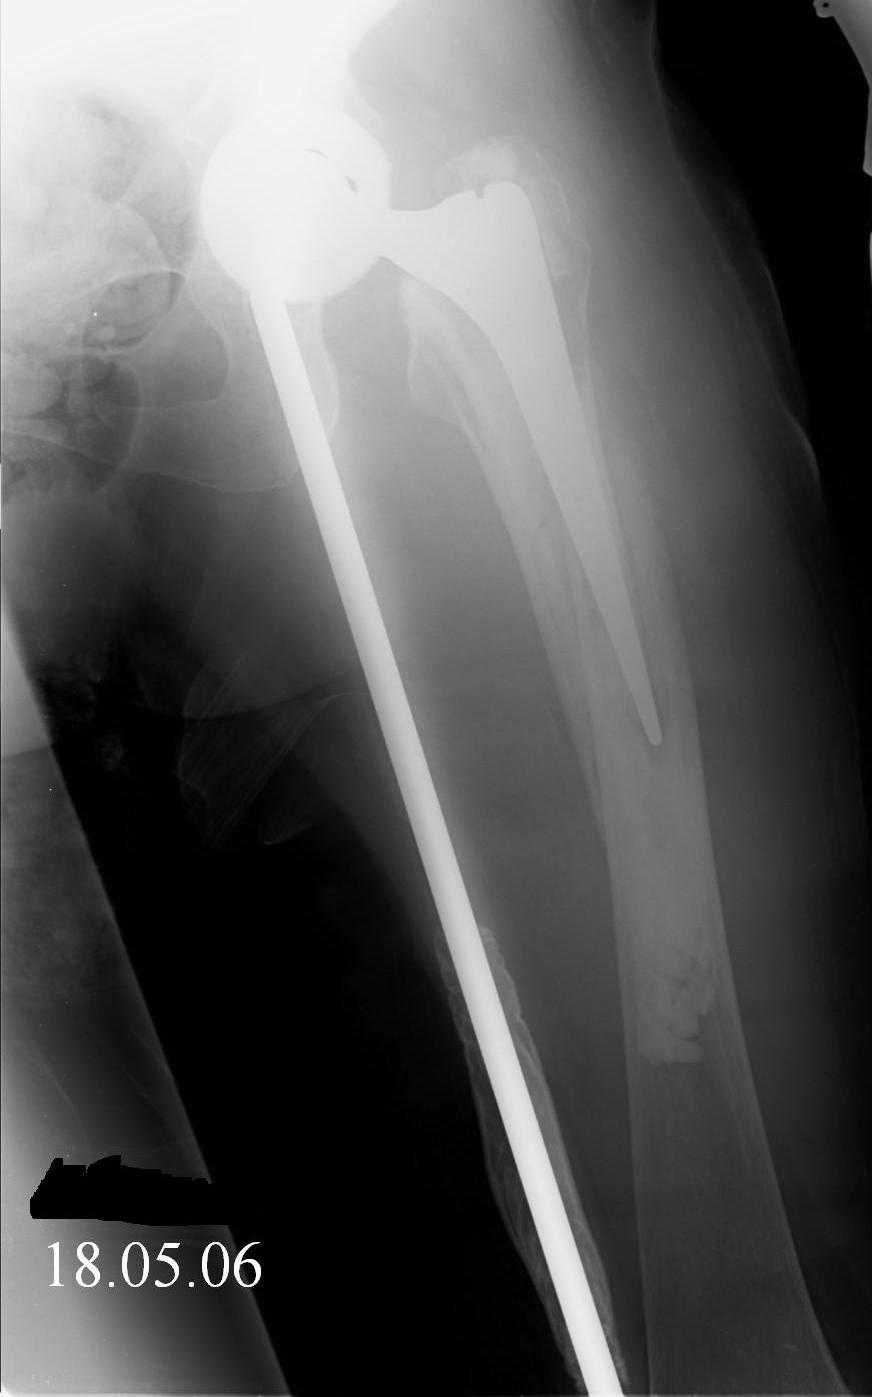

Спасибо за обсуждение. После нескольких дней тракции аппаратом сделали. Попытка закрытой репозиции не удалась из-за смещения по ширине, мешали фрагменты цемента. После их удаления репозиция получилась. Еще убрали немного цемента с ножки по латерльной стороне, чтобы обнажить 40-50 мм ее дистальной части, для плотной посадки гвоздя. Дальнейшее введение гвоздя было несложным. Протез показался нам стабильным в проксимальной части как латерально, так и медиально. Картинки в приложении.

THX for the discussion. After few days of traction by ex-fix the surgery was performed. An attempt of closed nailing was unsuccesful because of fragment translation, which was blocked by cement fragments. After removal of broken cement pieces reduction was reached "automagically". Also some cement from lateral part was removed by

chisel to expose distal 40-50 mm of the stem to allow tight fit of the nail. Further fixation by the nail was pretty easy and straightforward. Images attached. The stem looked stable in its proximal part both laterally and medially. Comments/critics are welcome.